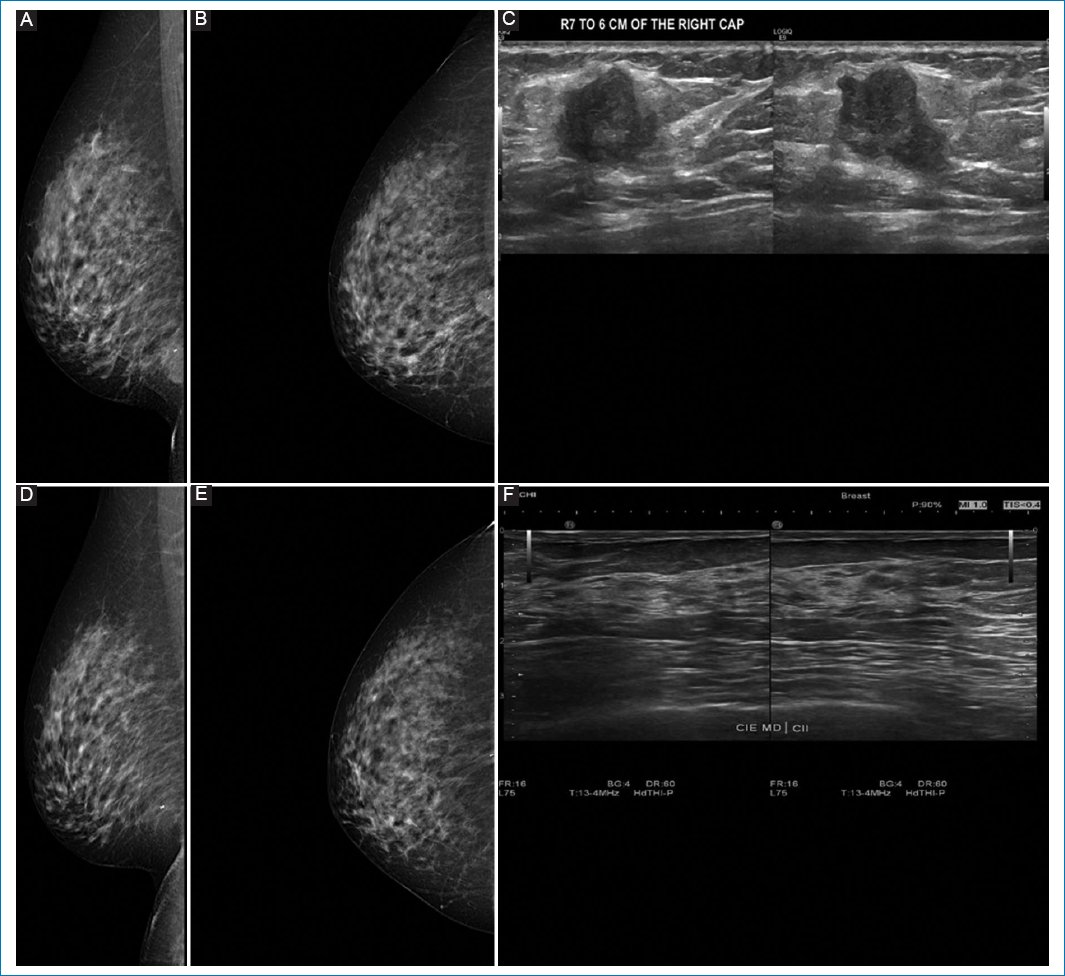

Pathologic response by imaging was classified as partial in 55.8% of cases (Figs. 1 and 2), complete in 34.6% (Figs. 3 and 4), stable (Fig. 5), or progressive disease in 9.6%. By pathology (RCB), response was complete in 53.8%, partial in 34.6%, and progressive in 11.5% (Fig. 6).

Figure 4. A-C: pre-neoadjuvant images. D-F: post-neoadjuvant images. 56-year-old female, diagnosed with infiltrating ductal carcinoma, grade II in right breast. Clinical stage IIA by T2 N0 M0, estrogen receptor 0%, PR 0%, human epidermal growth factor receptor 2 negative, and KI 67 5%. A and B: preneoadjuvant mastography specimen, with irregular nodule in the upper outer quadrant. C: ultrasound specimen of the same patient, with irregular nodule in R10 at 50 mm from the nipple. D and E: correspond to the mastography. F: ultrasound showing only clip, which corresponds to complete response.